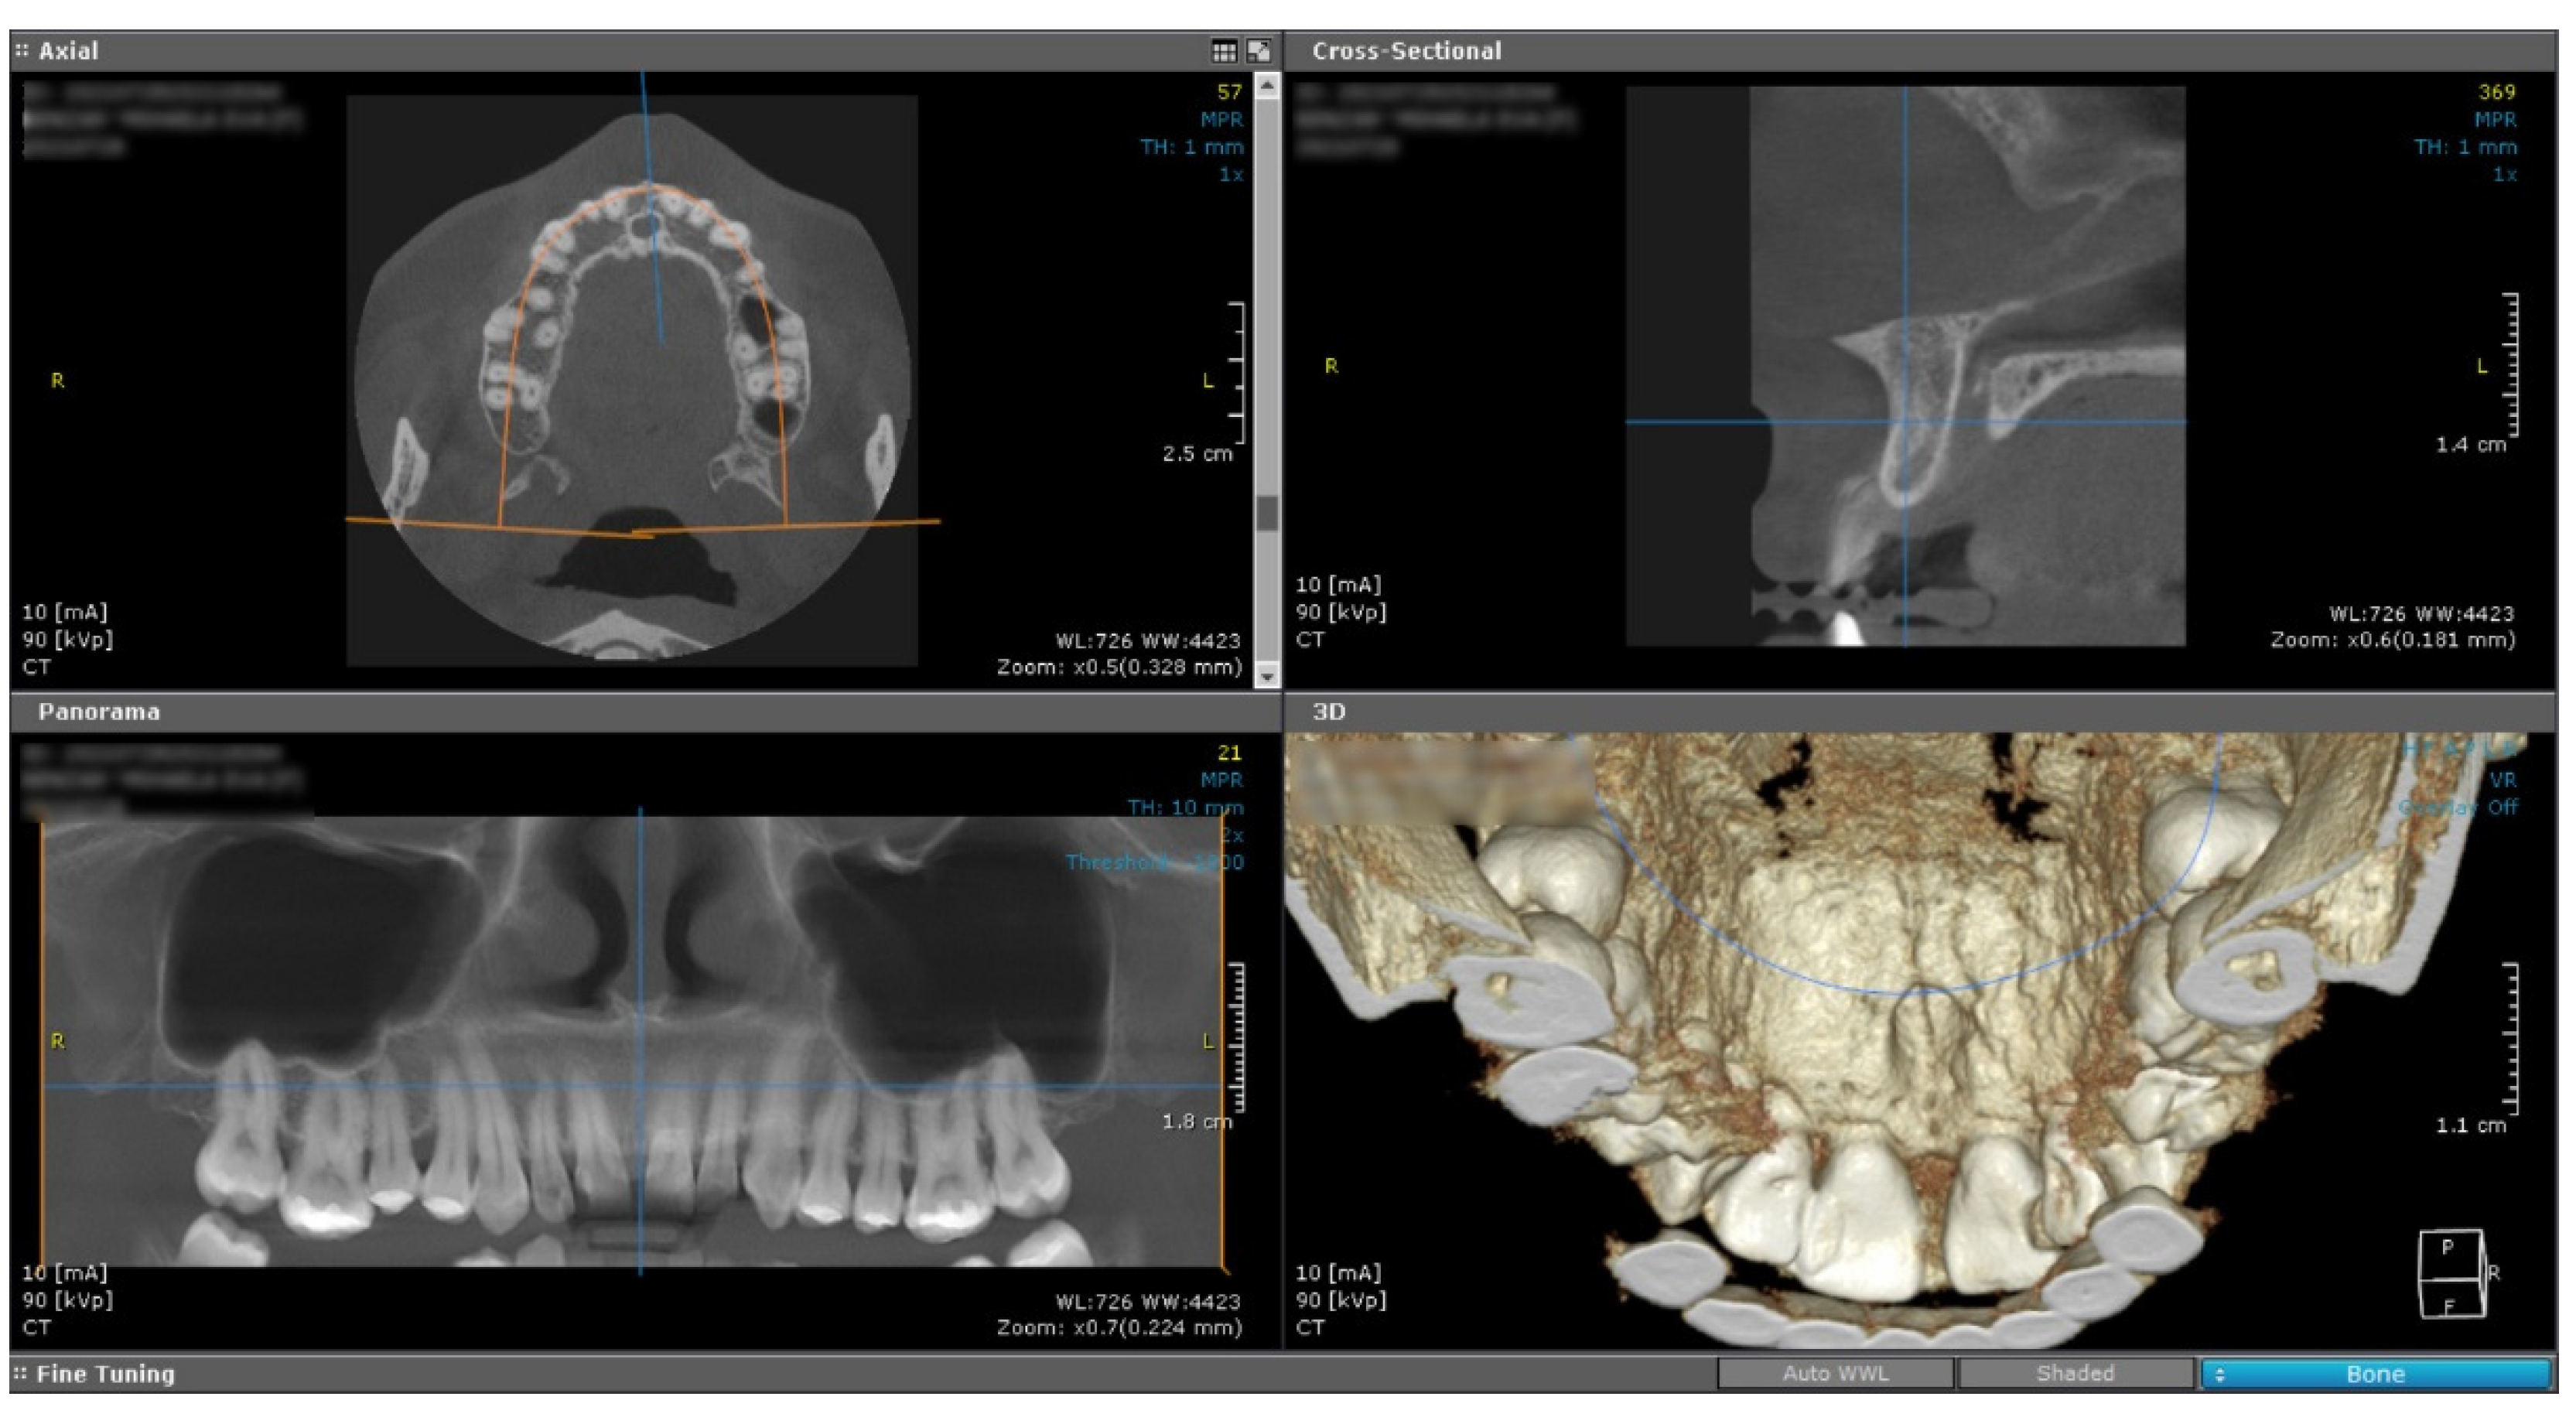

The cone beam computed tomography image (CBCT) does not reveal any changes of the subjacent bone structure in the anterior hard palate, suggesting the sole involvement of the soft tissue (Figure 2).

Figure 2. Cone Beam Computed Tomography shows no underlying bone structure alteration.